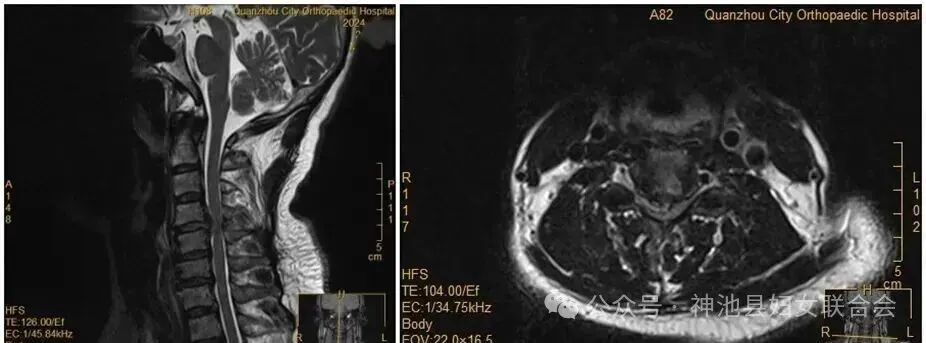

王女士術(shù)前MRI

沒想到,會(huì)診當(dāng)晚,王女士翻身拿手機(jī)的瞬間,雙手突然失去知覺——關(guān)鍵肌肌力降至1級(jí)或0級(jí),確診為癱瘓?!巴茰y(cè)是翻身時(shí),脫出的椎間盤突然進(jìn)一步卡壓到脊髓神經(jīng),引發(fā)了急性癥狀?!贬t(yī)生表示。

雖然已經(jīng)出現(xiàn)了癱瘓,王女士仍然懼怕手術(shù),不愿意接受手術(shù)。經(jīng)過醫(yī)務(wù)團(tuán)隊(duì)及王女士家人耐心解釋及勸解后,王女士才愿意接受手術(shù)治療。醫(yī)院為王女士緊急實(shí)施手術(shù)。手術(shù)順利,經(jīng)過一段時(shí)間恢復(fù),她的肢體功能逐漸回歸正常。